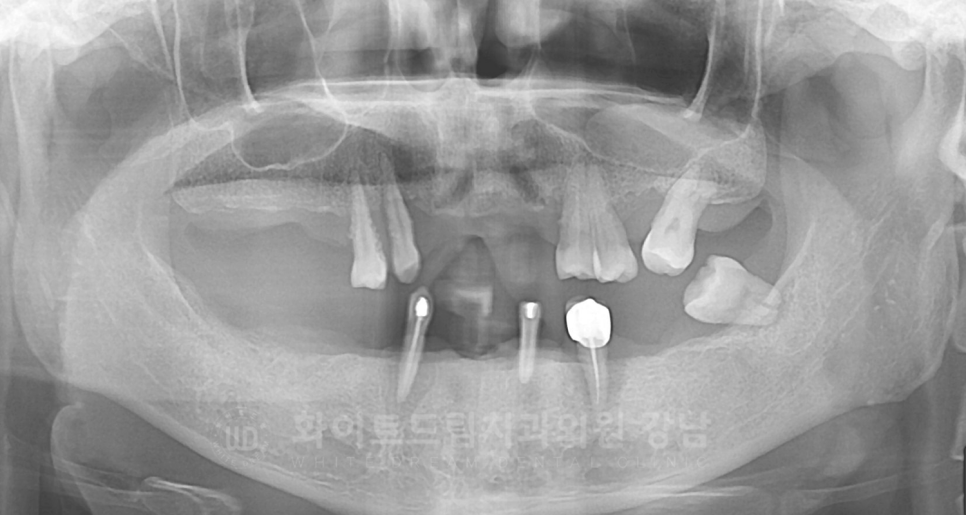

X-RAY 사진을 보면 대부분의 치아가 빠진 상태이고,

그나마 남아있는 치아들도 잇몸뼈에 겨우 매달려 있어 굉장히 심하게 흔들리고 있는 상태였습니다.

심한 치주염으로 인해 대부분의 치아가 빠진 것인데요.

상/하악의 맞닿는 치아가 한 부분밖에 없어 이 부분으로 조금씩 식사하며 지내셨다고 합니다.

강남역 임플란트 치과, 화이트드림치과 강남 전체 임플란트 사례 (진료 전)